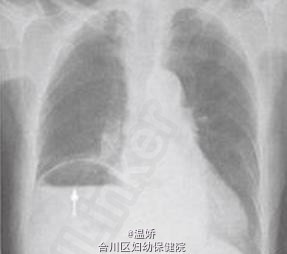

巨大食管裂孔疝嵌顿一例

男性,84岁。因“餐后突发右侧胸闷胸痛3d”来院求治。疼痛为持续性,伴恶心,无呕吐及发热。发病以来仅能进少量流质,排大便1次。既往有冠状动脉粥样硬化性心脏病史10余年,5年前曾因食管裂孔疝经左胸行疝修补术。

巨大食管裂孔疝。